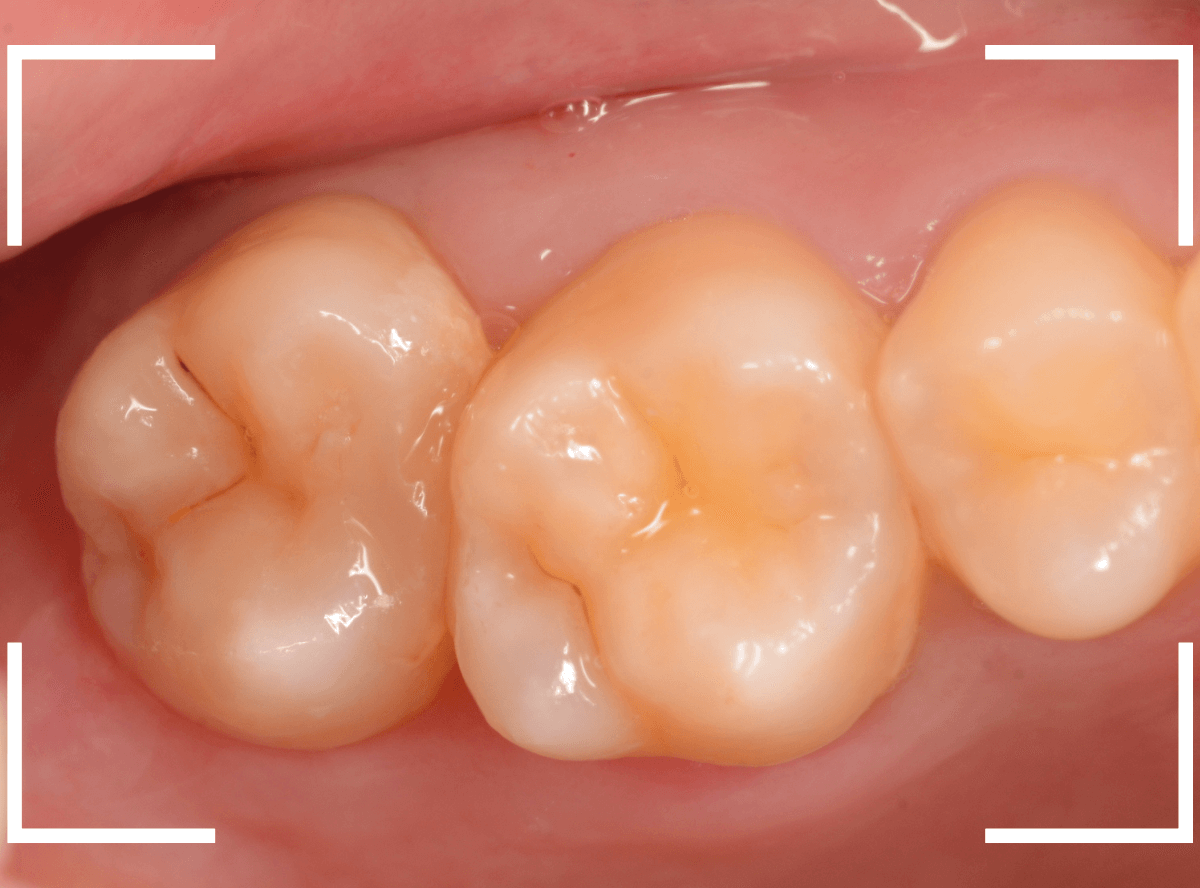

Case.22 痛みはないけど、歯のすきまから大きな虫歯

上の小臼歯の間が虫歯になっていた患者さんです。

症状はありませんし、見た目からも虫歯があるかはわかりませんでした。